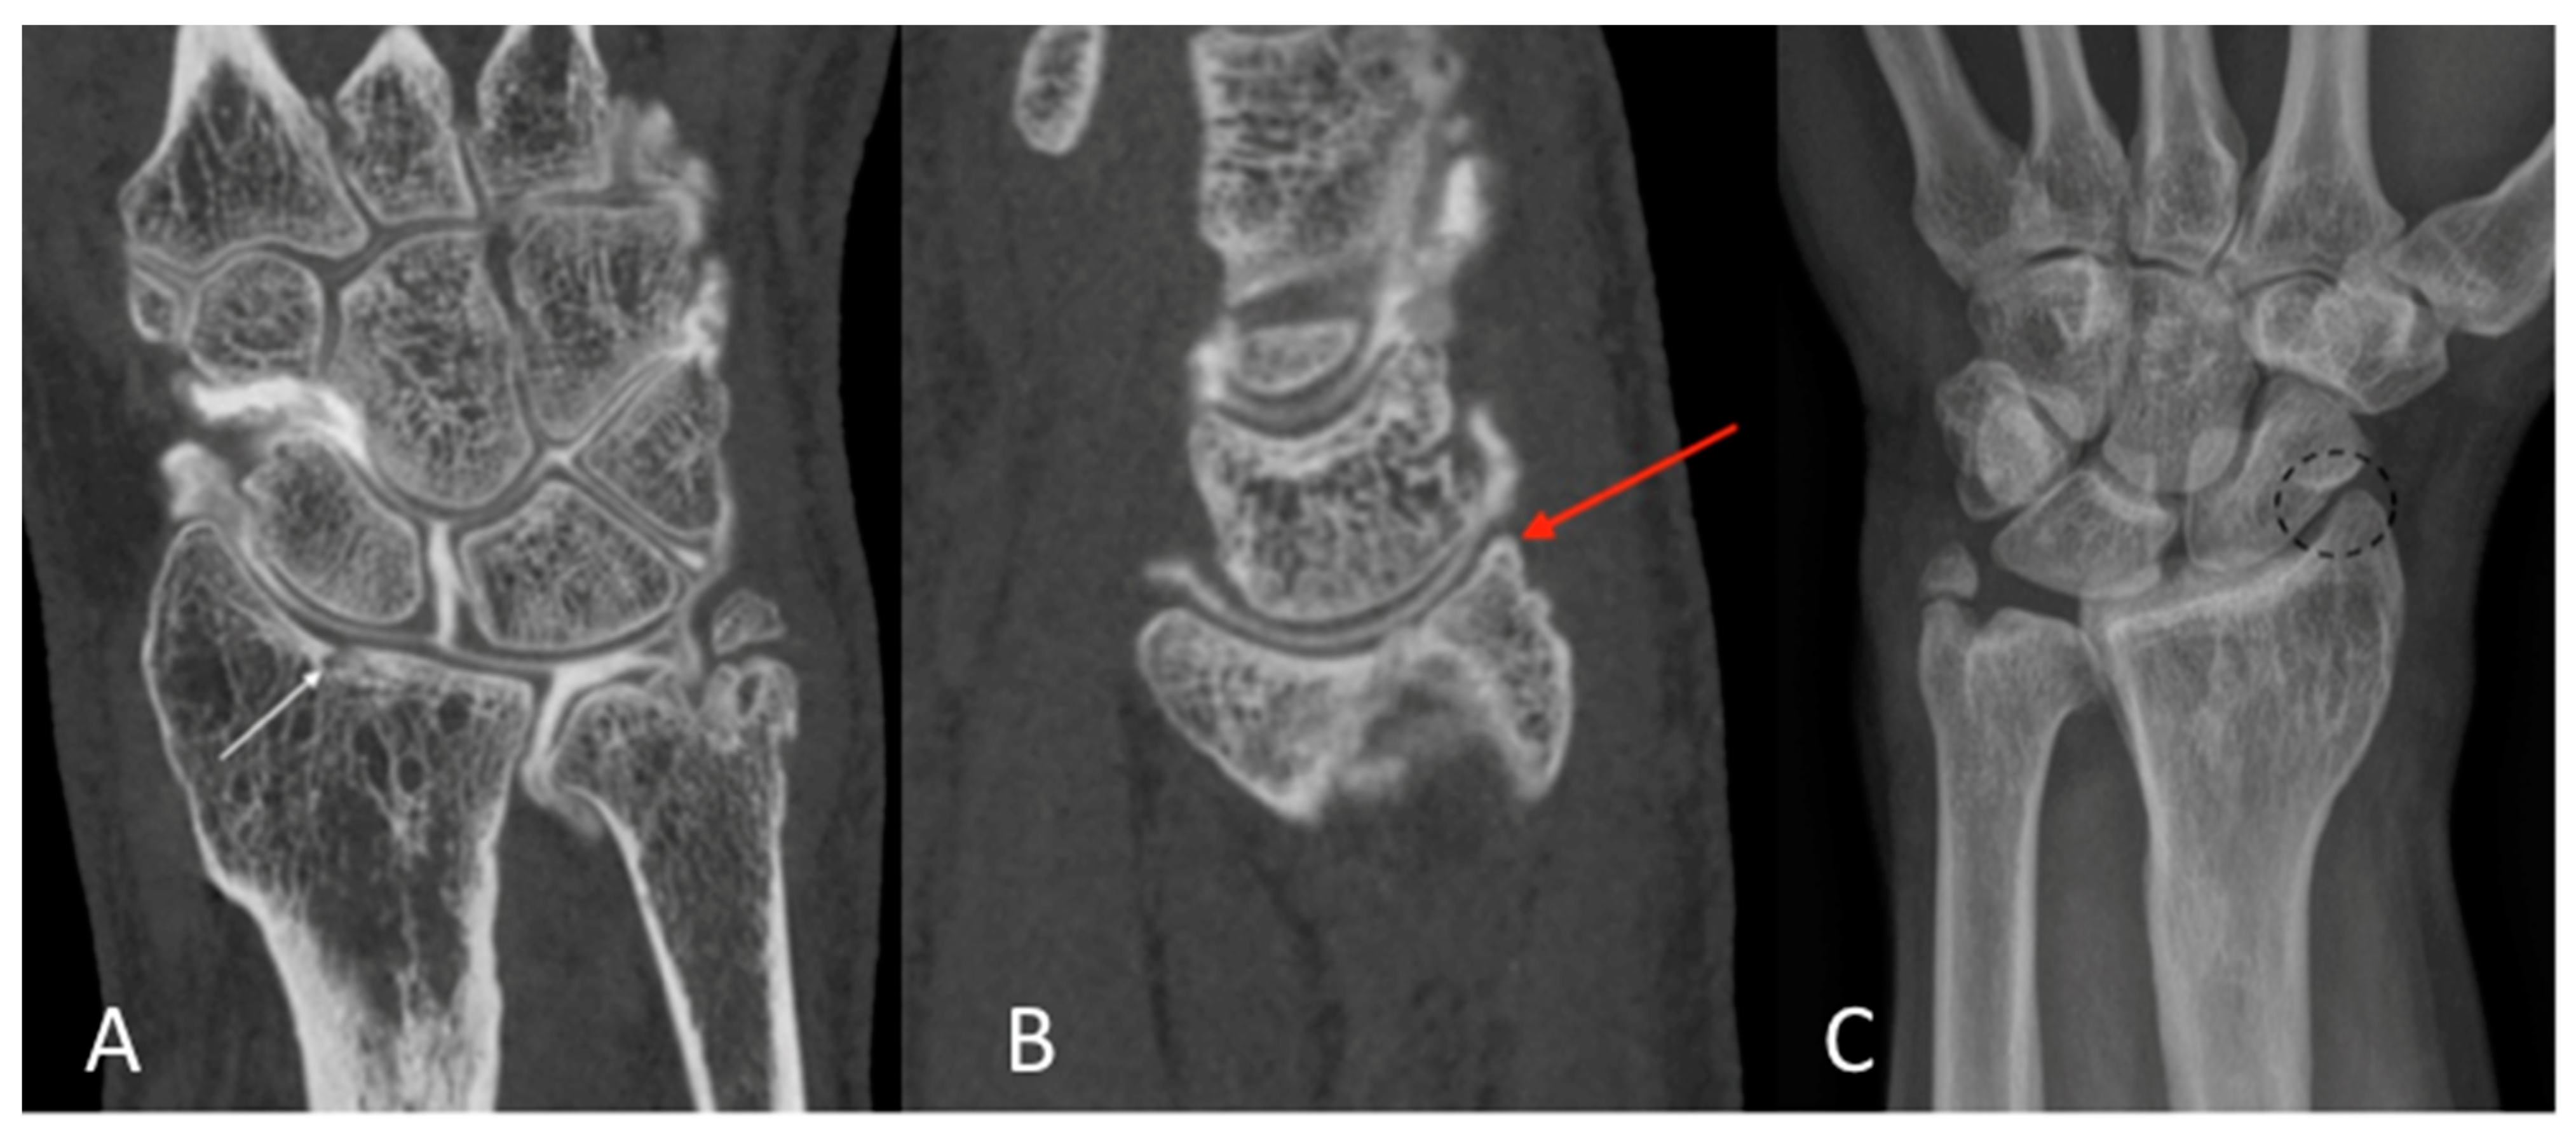

1. Introduction

2.1. Patient Population

2.3. Qualitative Image Analysis for CBCT-A